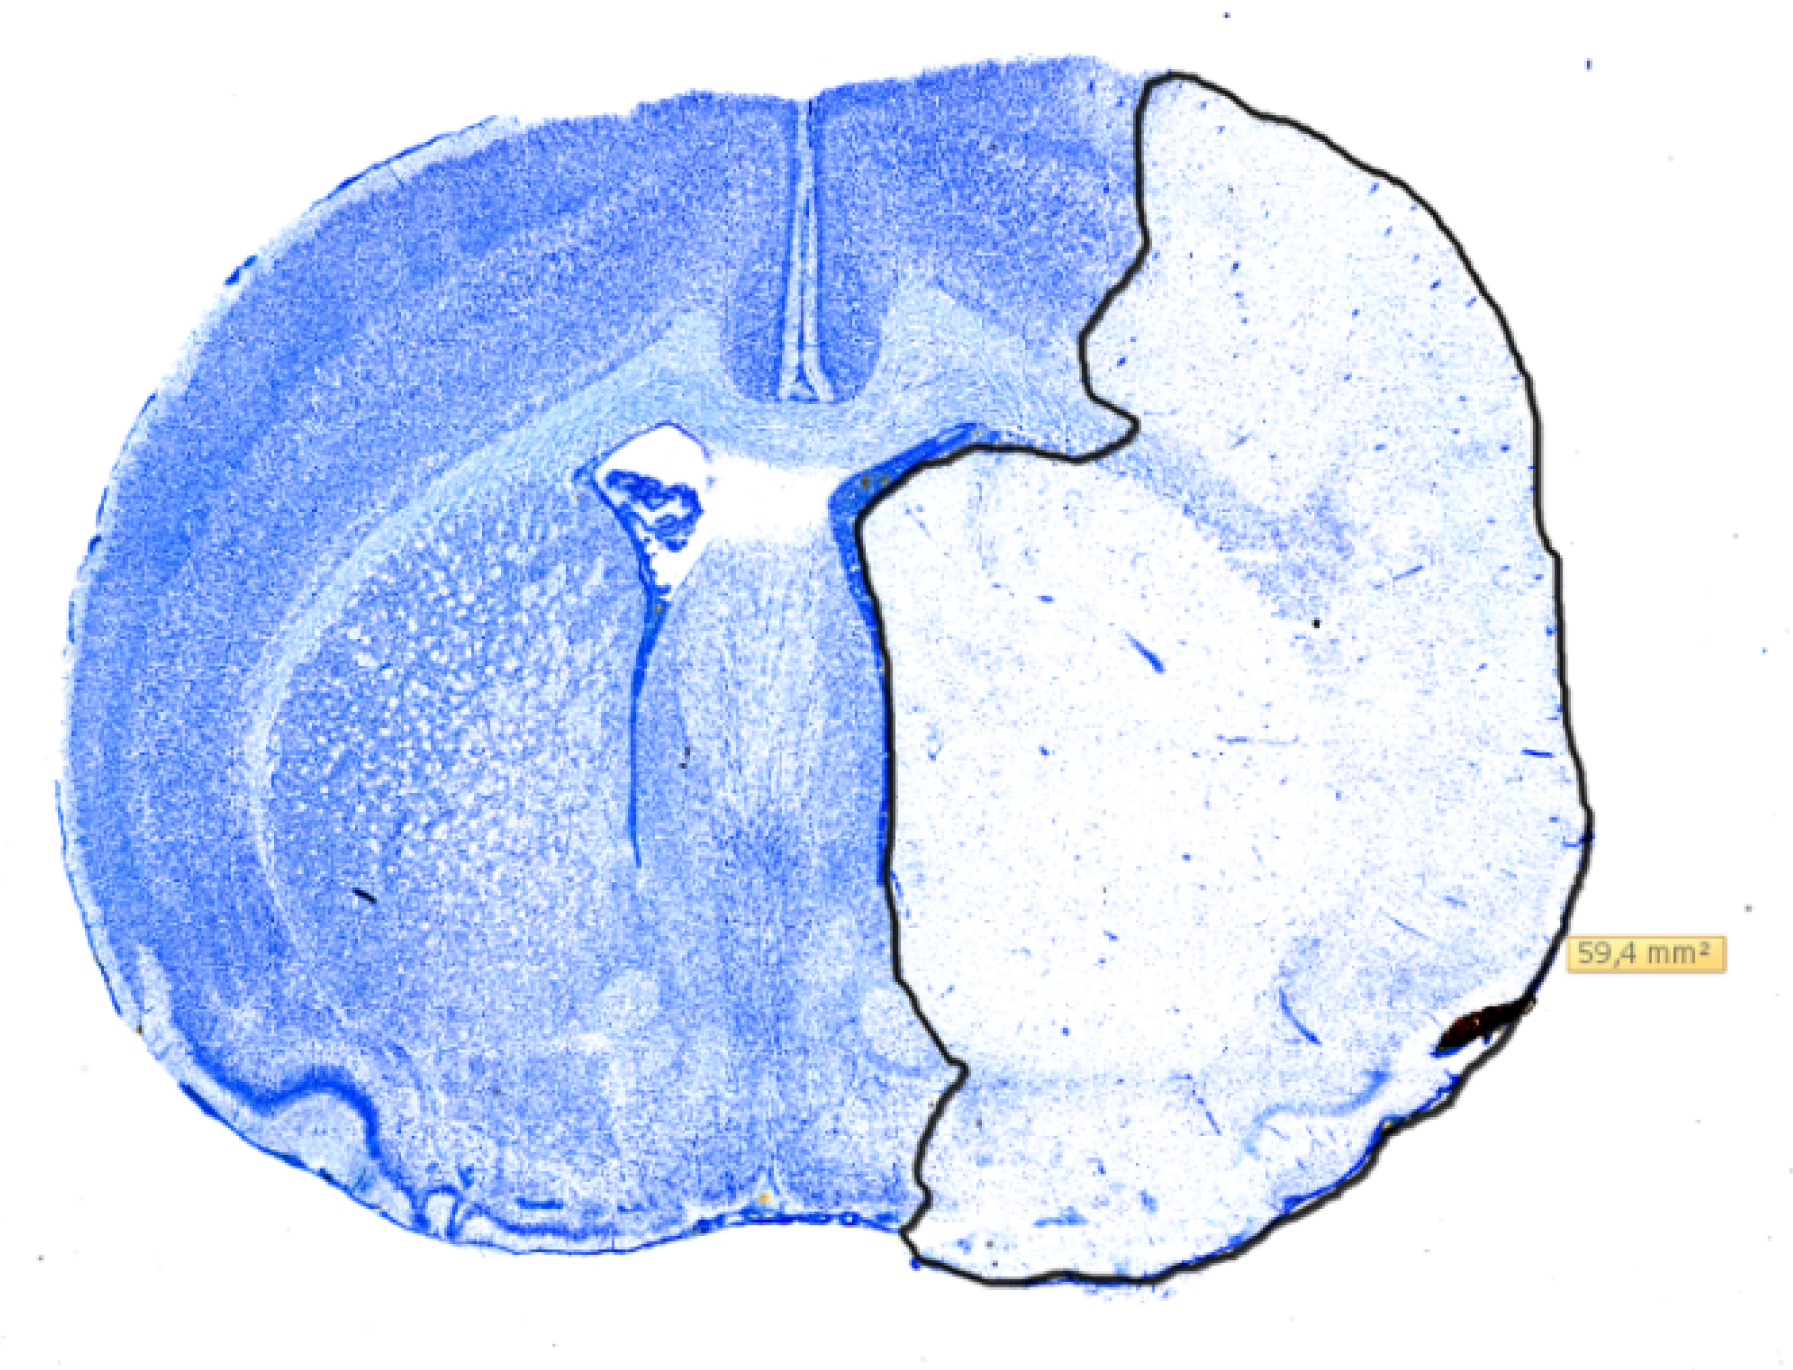

2.3. Histology

4.4. Infarct Volumetry